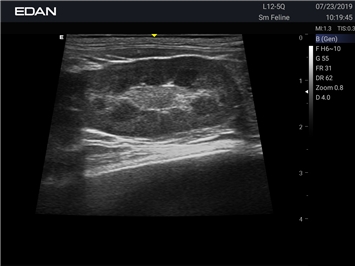

Ветеринарный ультразвук одним нажатием. Система Acclarix AX2 VET разработана с целью обеспечить бескомпромиссную производительность по доступной цене. Наличие уникальных двойных аккумуляторов в легком корпусе массой 4,5 кг из магниевого сплава позволяет системе Acclarix AX2 VET удовлетворять все потребности ветеринарных исследований, сохранив низкую стоимость.

EDAN Acclarix AX2 VET представляет собой специализированную ветеринарную ультразвуковую систему, сочетающую высокую производительность с доступной ценой. Благодаря продуманной конструкции и передовым технологиям, система обеспечивает качественную диагностику животных различных видов.

• Высокое разрешение для детальной диагностики

• Улучшенная визуализация глубоко расположенных органов

• Непрерывная автоматическая оптимизация изображения

• Адаптация к особенностям анатомии разных видов животных

• Повышенная точность исследований